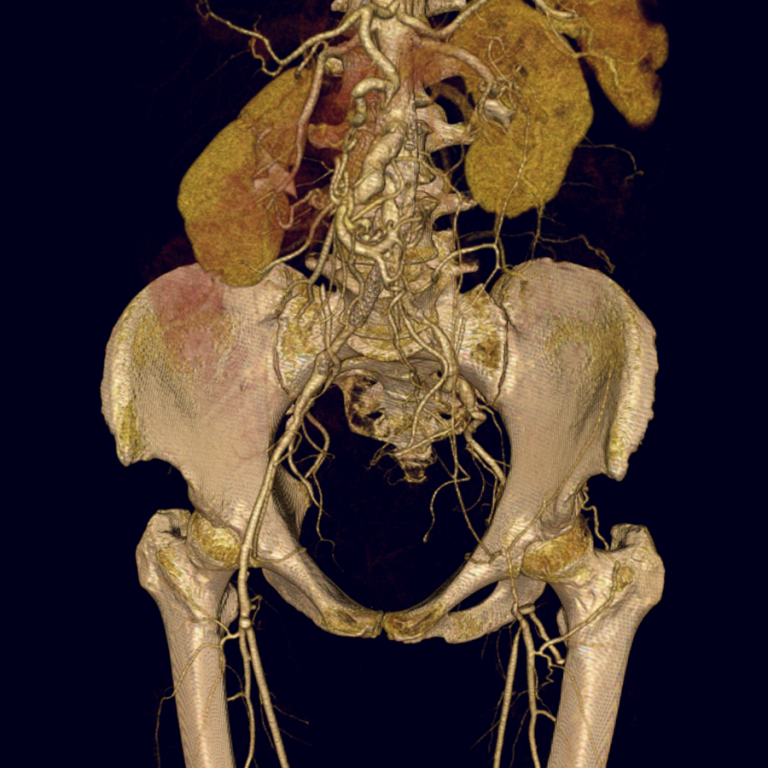

Thank you for your interest in cardiovascular imaging at the University of Wisconsin School of Medicine and Public Health, Department of Radiology. The Cardiovascular Imaging Section has long provided innovative, advanced clinical care in non-invasive cardiovascular imaging, including cardiac magnetic resonance imaging (MRI), magnetic resonance angiography (MRA), cardiac and coronary computed tomography (CCTA), and computed tomography angiography (CTA).

The volume of clinical studies has grown continuously and we now perform over 5000 non-invasive cardiovascular CT and MR studies each year. The members of our section are very active and renowned locally, nationally, and internationally with over 550 peer-reviewed publications, 30 book chapters, 1200 scientific presentations, and 50 patents. Time-resolved contrast-enhanced MRA (TRICKs), pulmonary MRA for pulmonary embolism, non-contrast-enhanced MRA, four-dimensional (4D) flow MRI, low-dose CTA and CCTA, and 3D printing are just a few examples of the innovations developed by our group that have had a significant impact on clinical care locally and beyond.